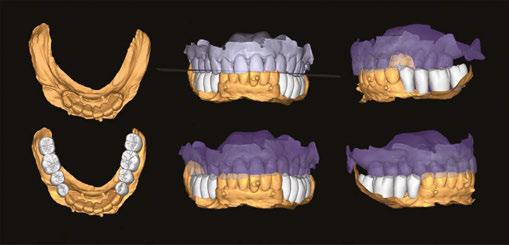

When imported into a design software (e.g., Exocad), the OPTISPLINT scan will produce a digital file of implant positioning. Additional records include facial records, soft tissue records, and tooth/occlusal records (Figure 6).

After all the records are acquired, the scans may then be aligned and the patient’s implant prosthesis can be designed and fabricated (Figures 7A-7F). The OPTISPLINT technique enables clinicians to utilize a fully-digital workflow for a fraction of the cost of other digital methods. Patient factors are able to be eliminated as the OPTISPLINT can be scanned extraorally with the added benefit of acting as a verification jig prior to prosthetic delivery.

Figures 7A-7F: 7A. Alignment of facial record to teeth, to aid in smile design and tooth setup. 7B. Detecting implant position via scan region of OPTISPLINT jig. 7C. Alignment of patient’s teeth to soft tissue, to allow tooth setup at correct vertical dimension. 7D. Alignment of implant position to soft tissue. 7E. Digital design of patient’s prosthesis. 7F. Final prosthetic delivery